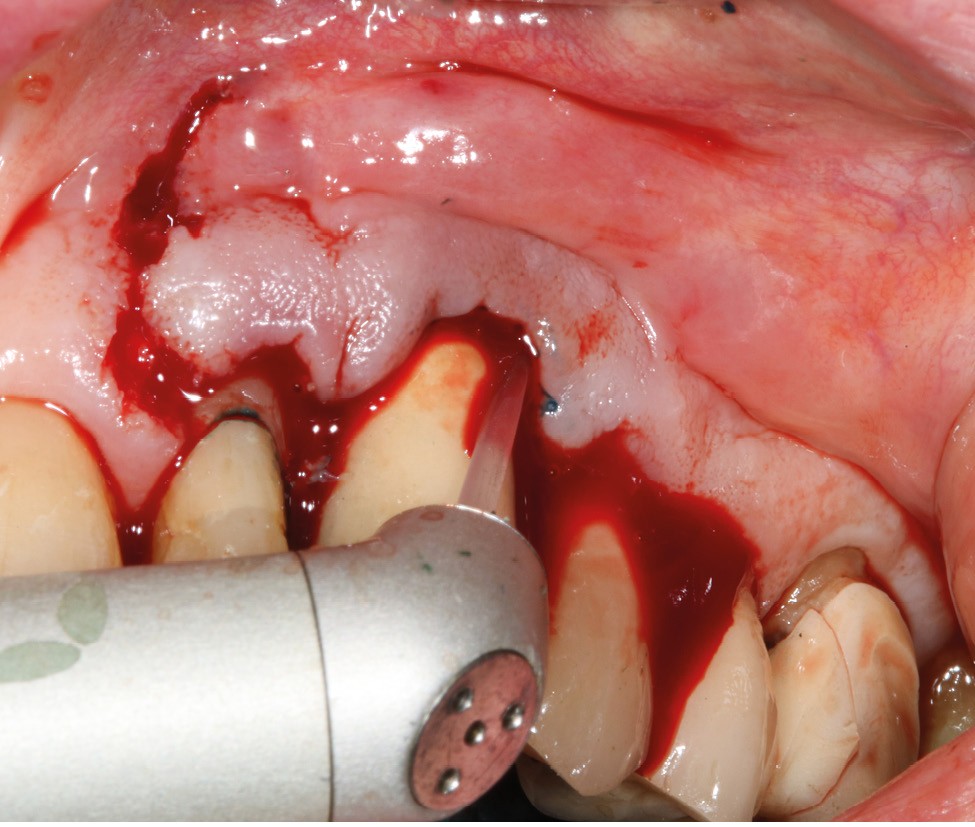

Le patient

- 70 ans

- Pas d’antécédents médicaux

- Ne fume pas

- Hygiène correcte

L’implant

- Site 23

- Mis en place il y a 12 ans